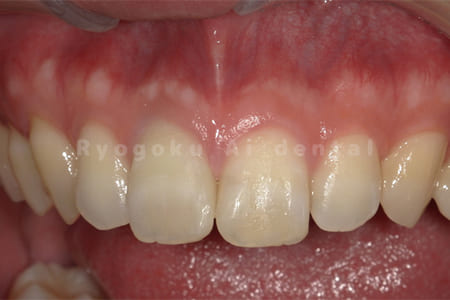

Case01

- 原因

- 歯の神経が死んでしまったことによる変色

- 治療内容

- ブリーチングのみ

- 治療費用

- 55,000円

上顎前歯部の歯の神経が死んでしまったことによる1歯の変色をブリーチングにより改善したケース。